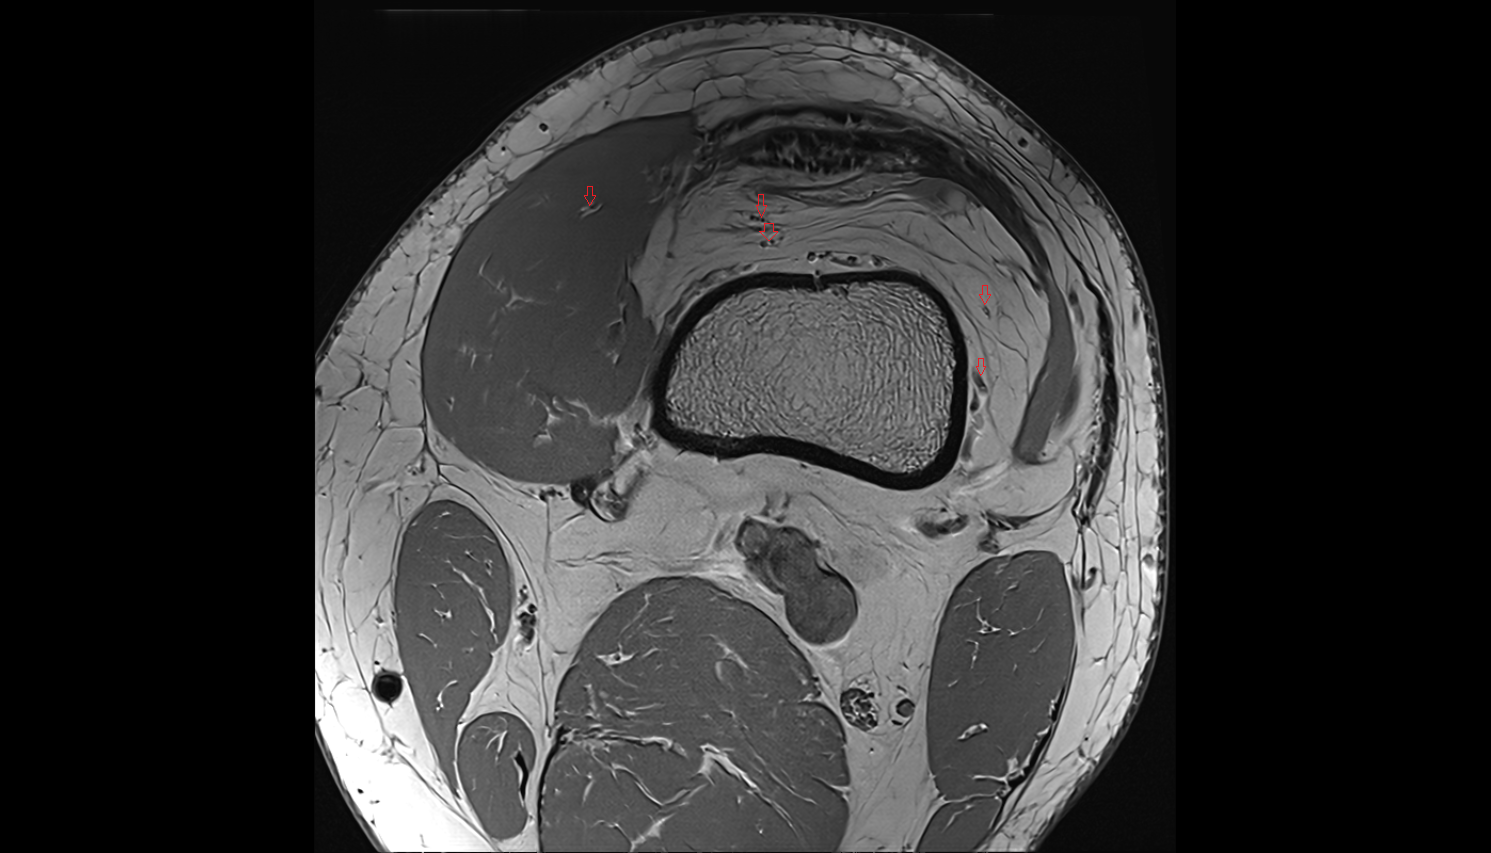

- Knee Joint